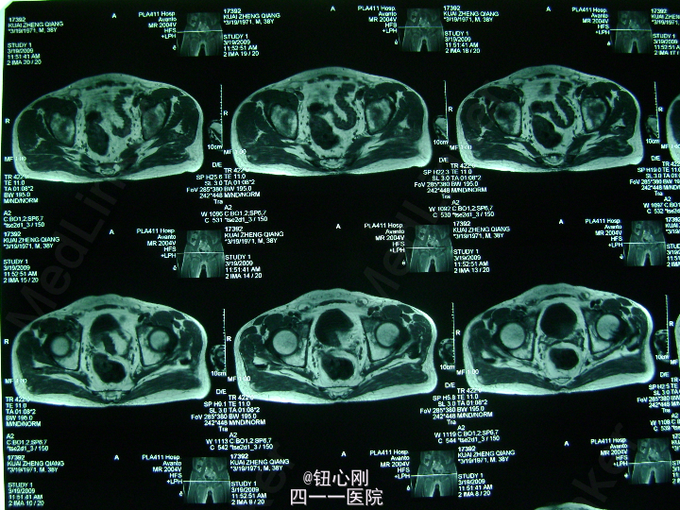

男,38岁,主诉全身多处骨关节疼痛5年。5年内身高降低5厘米,活动后全身关节疼痛加重,休息后减轻。疼痛以腰椎,全身大关节为主。既往体健,否认有肾功能不全及胃肠道病史,肝胆胰腺病史,无激素及其他特殊药物使用史。无毒物接触史。饮食正常,家族中无类似病史

查体间:略有驼背畸形,全身大关节及脊柱活动性降低,大关节处有明显叩压痛。 辅助检查:三大常规,肝肾功正常,血沉正常,各肿瘤指标正常,钙正常,血磷减低(0.44mmol/L),骨特异性碱性磷酸酶升高(99.95ng/L),PTH、CT正常,尿本周蛋白(-),血清蛋白电泳正常,无M蛋白,血皮质醇正常。 胸片,心电图,肝胆胰脾双肾B超正常。

病史特点:1、壮年男性,以全身多处骨痛为主,伴身高降低为主诉;2、体检可见:驼背畸形,脊柱及四肢大关节处活动降低,有叩压痛;3、辅助检查提示:血磷减低,血钙正常,影像学显示:全身骨骼骨质疏松改变,未见其它骨破坏。 鉴别诊断:排除骨髓瘤,转移性肿瘤,甲状旁腺亢进,肾性骨病,原发性及药物性骨质疏松 诊断:成人低磷性骨软化症 治疗:予以钙片、骨化三醇,中性磷酸盐口服